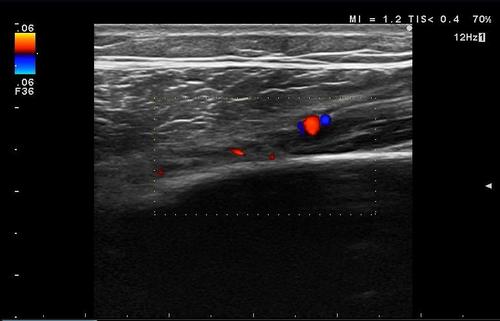

ふくらはぎの肉離れ

西武新宿線 東伏見駅南口『まる接骨院』です。 ここ数日、気温の低下からか、「肉離...